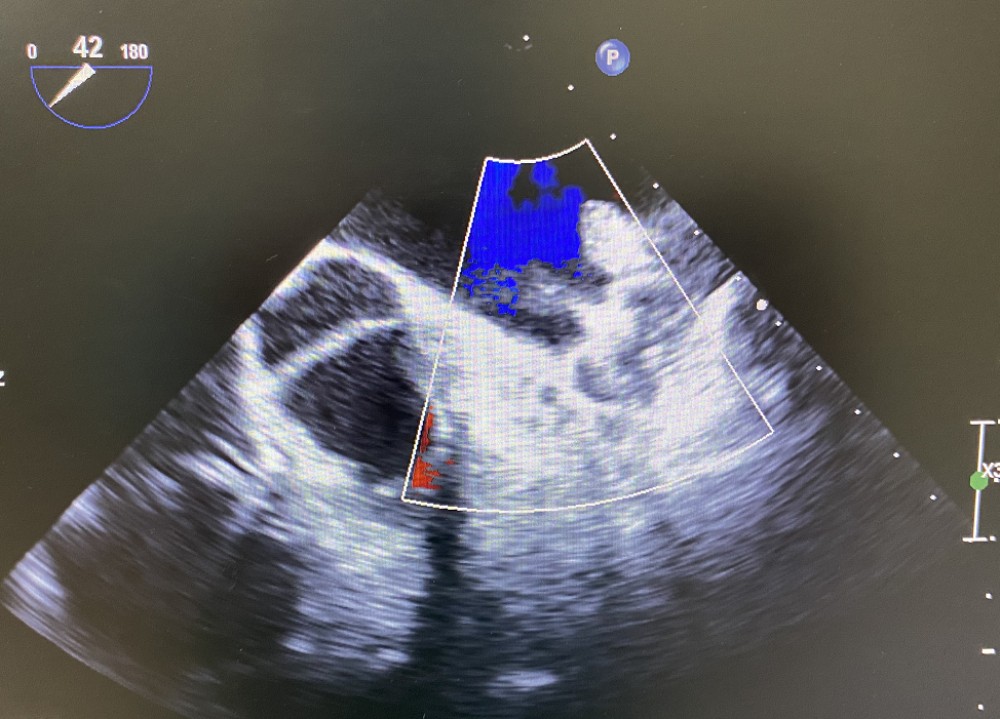

术中TEE影像图